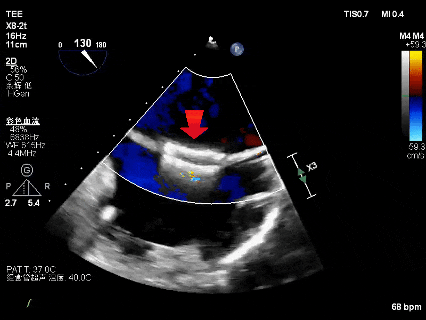

选择27mm Watchman FLX(Boston Scientific)左心耳封堵器,置入顺利,位置良好,压缩比合适,无残余漏,牵拉试验稳定。完成后交换输送鞘,选择D‐Shufo(Vickor)卵圆孔封堵器(30mm),完全覆盖ASA与PFO,TEE无残余分流。

成功置入左心耳封堵器

成功置入PFO封堵器

植入后左心耳封堵器(TEE)

置入后PFO封堵器(TEE)